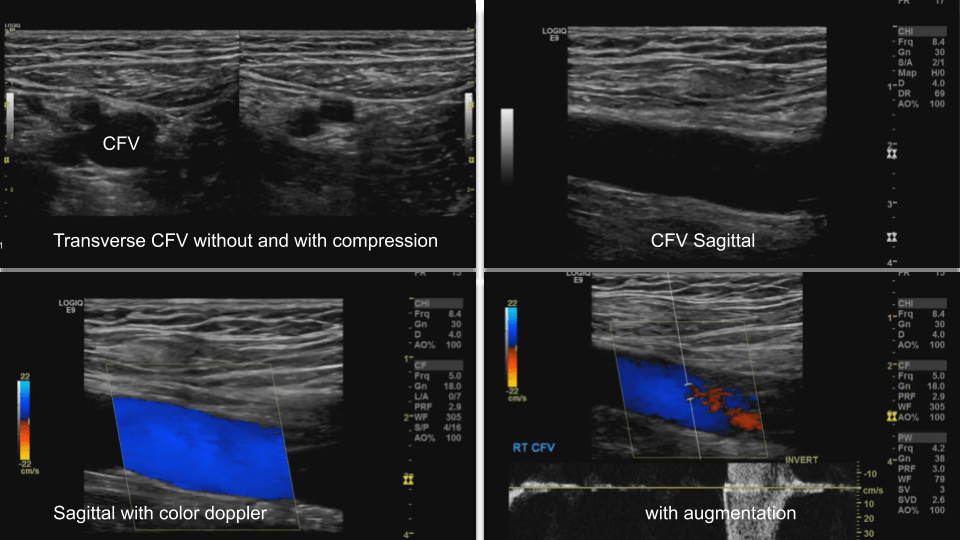

Common Femoral Vein: Dual image with compression, grayscale, color doppler, color doppler and pulsed wave doppler